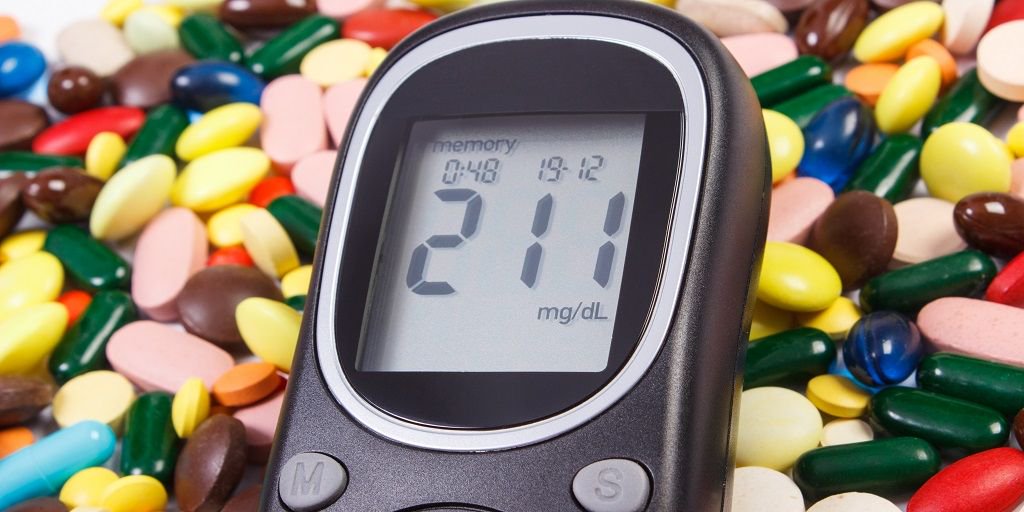

Chronic kidney disease, congestive heart failure, or chronic liver disease patients benefit from

#metformin use. http://bit.ly/2ifc0vx pic.twitter.com/FATBIZ9aSL

Physicians should prescribe

#metformin to type 2 diabetes patients, according to new@ACPinternists recommendations. http://bit.ly/2hNSMB9 -